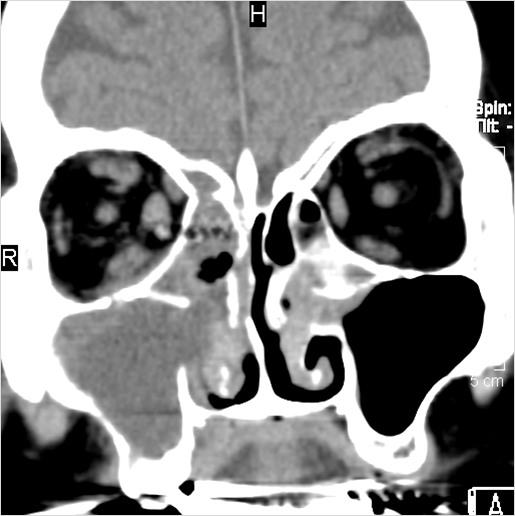

There is mucoperiosteal thickening in the sinuses.

There is a deeply infiltrating, necrotic or ulcerative process of the nasopharynx.

There is evidence of inflammatory changes within the parapharyngeal fat of the nasopharynx.